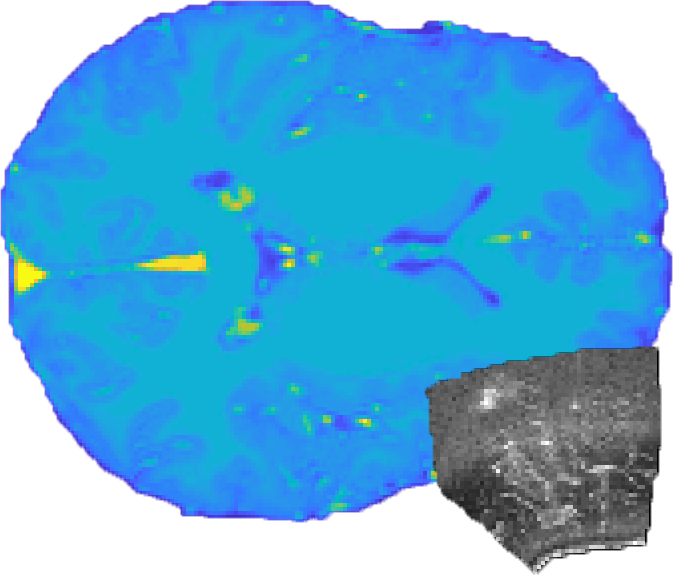

Refer to caption

Figure 2: Volumes and label map with (1) 80mm80𝑚𝑚-80~{}mm offset in x𝑥x direction, 0.1rad0.1𝑟𝑎𝑑-0.1~{}rad rotation around α𝛼\alpha and β𝛽\beta for the MRI (2) after initialization with our method and (3) ground truth provided by RESECT (4) distance map for surface (5) and foreground label.